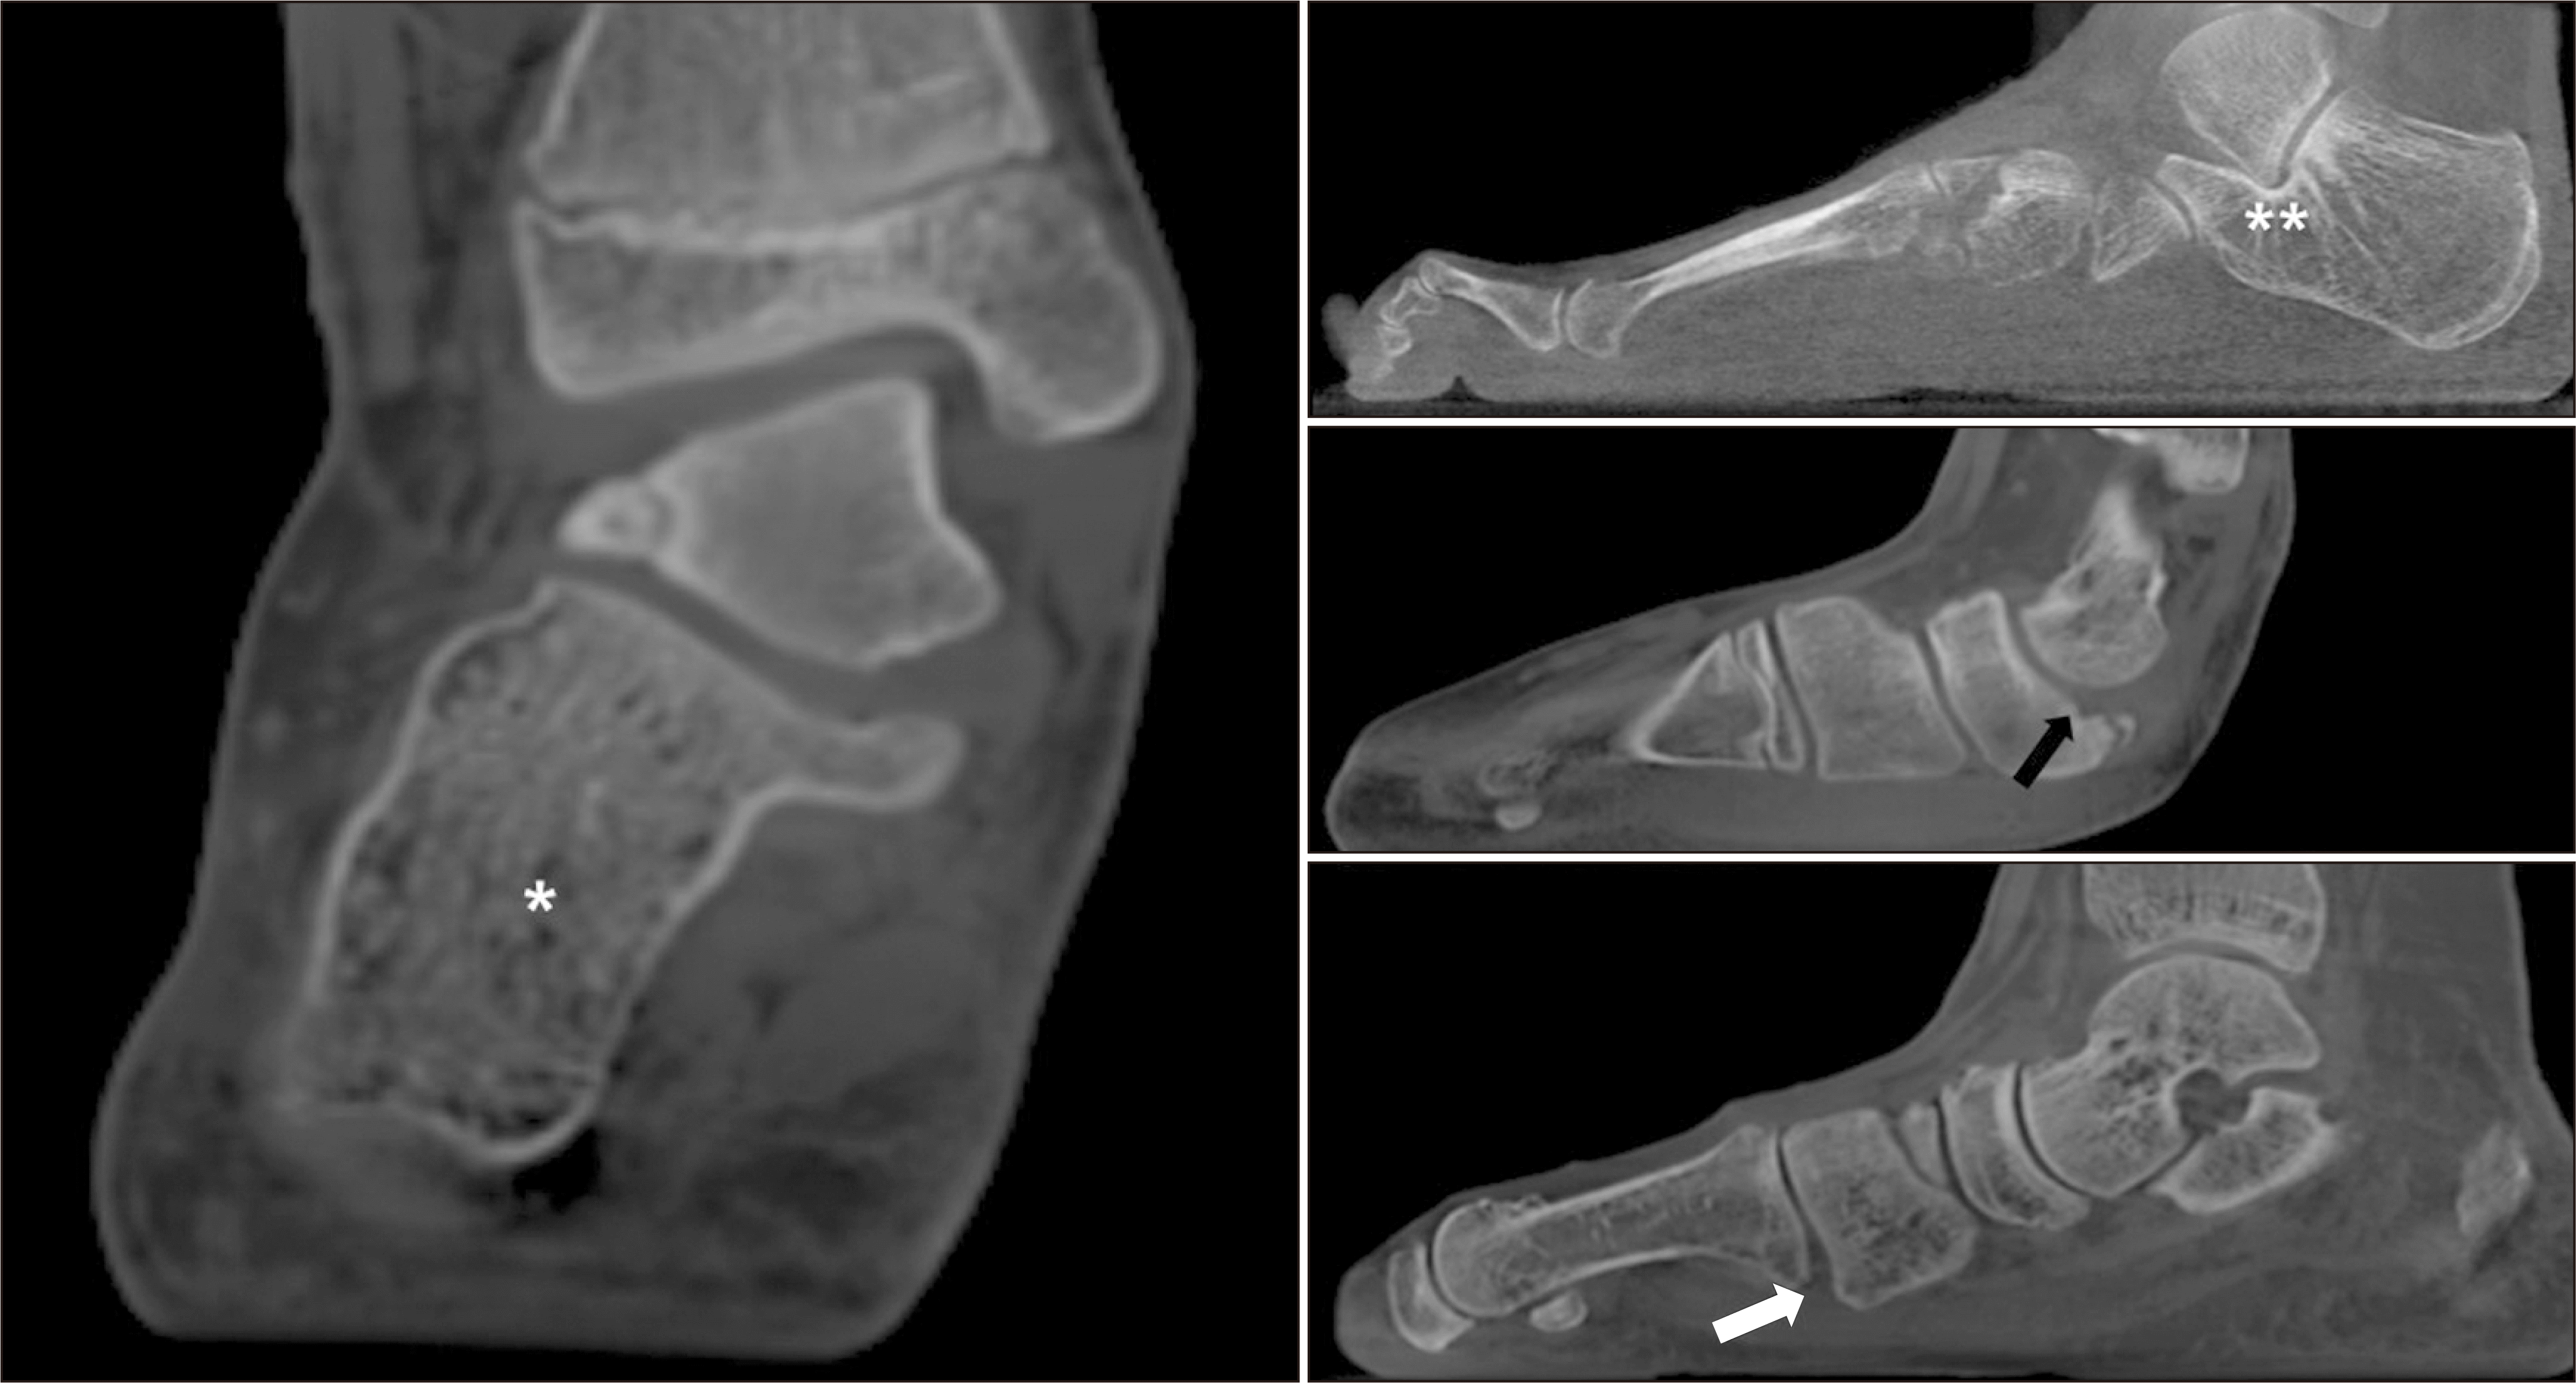

비록 평발 진단의 표준 검사는 체중부하 방사선 촬영이지만 여러 가지 한계점이 제기되어왔다. 가장 흔히 알려진 문제점으로는 촬영 기술과 환자의 자세에 의해 부정확한 검사가 이루어질 가능성이 있으며, 영상을 판독할 때 여러 조직들이 겹치면서 정확한 판독이 제한되는 점이다. 또한 단순 방사선 촬영을 통한 평가 방법은 변형의 정도를 과소평가하는 경향이 있다는 보고가 있다.11) 이에 따라 체중부하 전산화 단층촬영이 개발된 뒤 널리 시행되면서 편평족의 진단을 위해 많은 연구가 이루어지고 있으며 여러가지 장점들이 제시되고 있다. 대표적으로 체중부하 전산화 단층촬영은 3차원의 다면영상이기 때문에 단순 방사선 촬영에 비해 촬영 당시의 자세나 촬영 방향에 의한 오차를 최소화할 수 있으며, 영상을 판독할 때 여러 조직들이 겹치면서 발생하는 문제를 줄일 수 있다(Fig. 6).9,11) 많은 연구들에 의해 편평족의 평가를 위한 체중부하 전산화 단층촬영의 신뢰성(reliability)과 재현성(reproducibility)을 입증했으며, 단순 방사선 촬영이나, 비체중부하 전산화 단층촬영에 비해 구조적인 변형의 정도를 정량화하는 데 특히 뛰어나다고 보고된다.9,11-14) 특히 이 검사는 단순 방사선 촬영에 비해 관상면의 변형, 특히 거근관절의 탈구 혹은 아탈구를 확인하고, 분석하는 데 장점을 가지며, 거근관절의 아탈구에 의해 발생하는 비골하 충돌이나 족근동 충돌을 보다 직접적으로 확인할 수 있다.9) 또한 골구조의 겹침 없이 관절면을 평가할 수 있는 체중부하 전산화 단층촬영의 장점을 이용한 연구에 따르면 편평족이 있는 환자는 거골하 관절 자체의 외반경사를 가지며, 이러한 경향성을 파악하는데도 유용함을 보인다.15) 그 외에도 자동화된 프로그램을 통해 여러 지표들을 측정하고, 계산하려는 시도들이 있다. 대표적으로 발과 발목 오프셋(FAO, foot and ankle offset)이 있으며, 이는 발의 삼각대(tripod)와 발목관절의 중심 사이의 관계를 평가하는 지표로 여러 연구에서 변형과 수술 후 교정 정도를 평가하는데 유용함이 보고되었다(Fig. 7).16,17) Haleem 등18)은 체중부하 전산화 단층촬영이 단순 방사선 촬영에 비해 더 민감한 검사임을 보고하였고, Kunas 등19)은 정상적인 체중부하 상태에서 검사가 이루어지기 때문에 비체중부하 전산화 단층촬영에 비해 보다 더 정확하게 변형을 평가할 수 있다고 기술하였다. 따라서 최근 발표한 전문가 합의 그룹에서는 체중부하 전산화 단층촬영이 가능하다면, 편평족의 치료계획 수립을 위해 시행할 것을 권고하였다.9)

Figure 6

Weight bearing foot computed tomography showing hindfoot valgus (*) and sinus tarsi impingement (**). Medial column instability on talonavicular joint (black arrow) and tarsometatarsal joint with plantar gapping (white arrow).